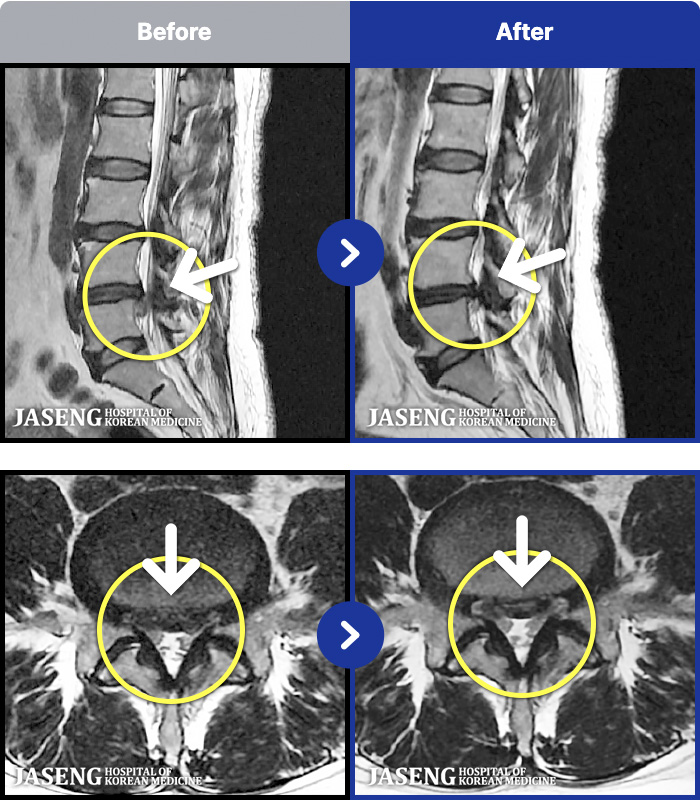

88 MRI ũ ʸ Ȯϼ.

ȯںп Ǹ ǿ ԿǾ, ο ġ ۿ Ƿ ġḦ Ͻñ ٶϴ.